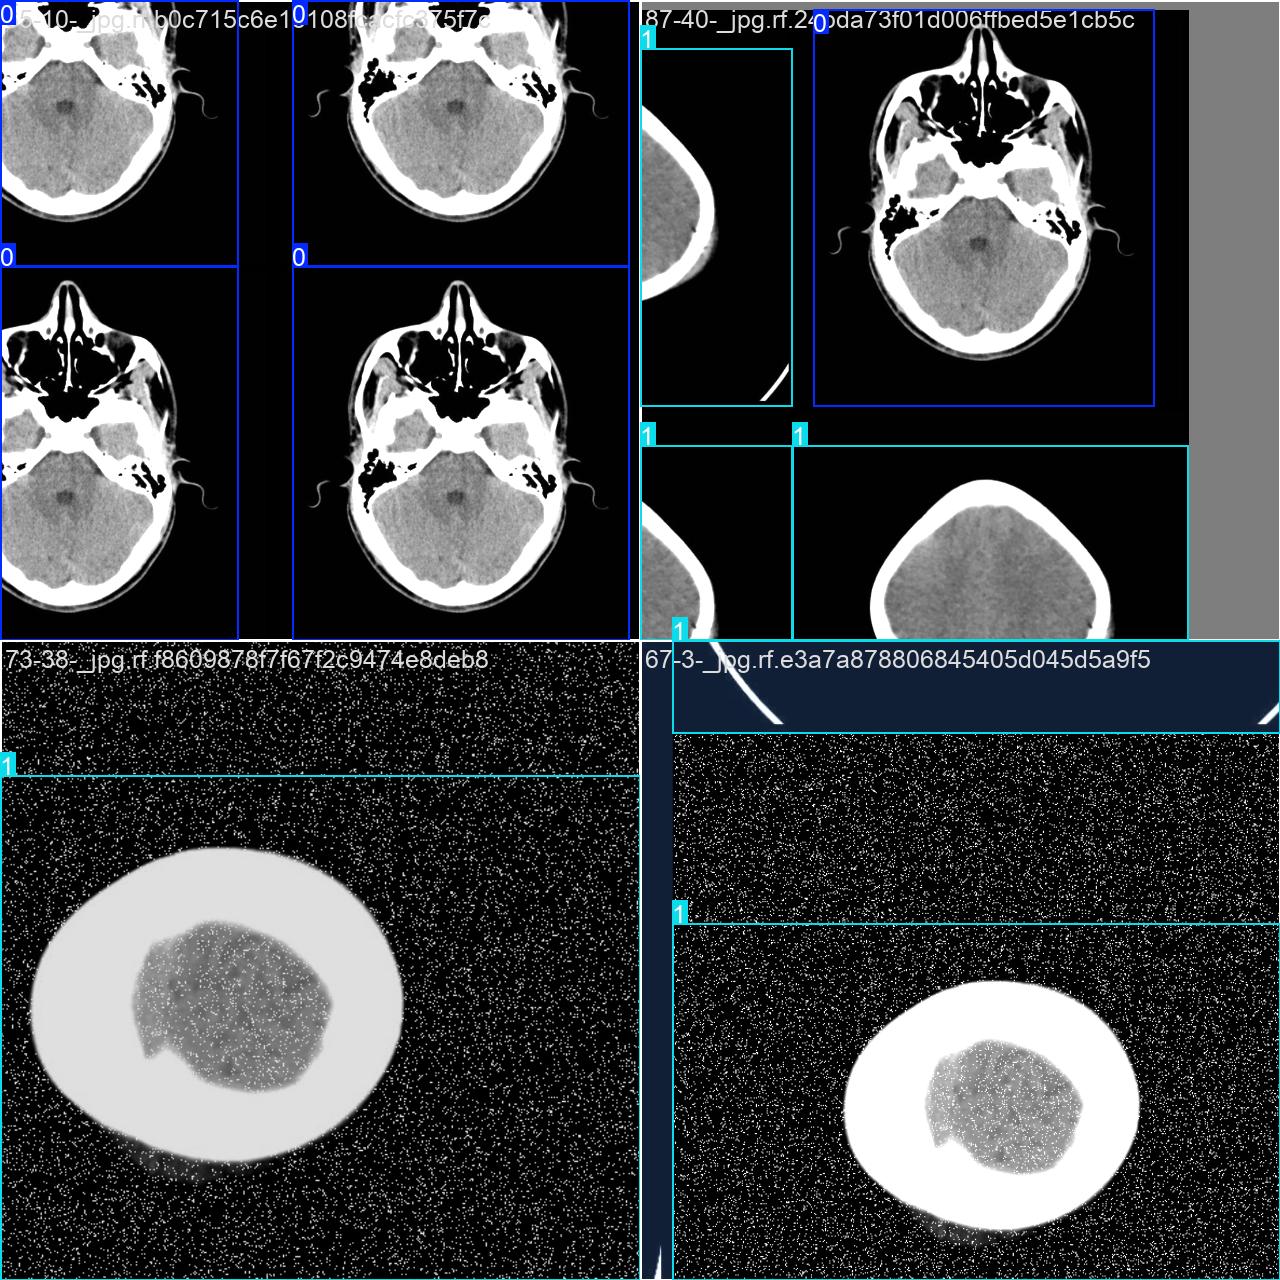

目标检测训练数据可视化

目标检测训练过程中,模型对数据的可视化结果,主要展示了多个类别目标的检测边框和类别标注情况。整体检测表现较好,但可以通过优化标注和模型训练进一步提升精度和鲁棒性。